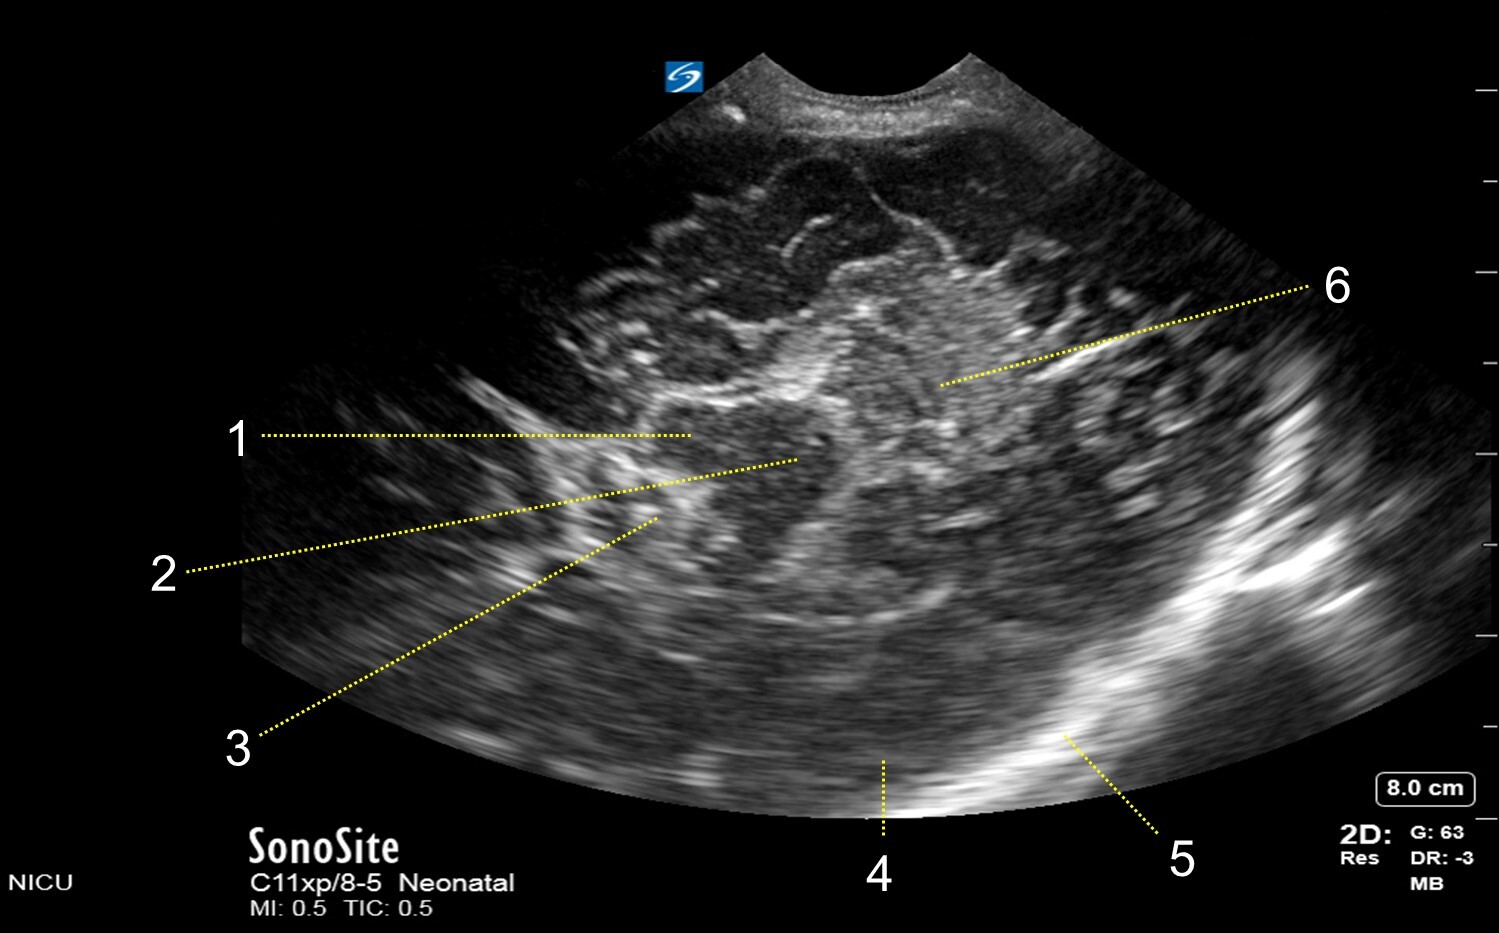

Neonatology Mastoid Fontanel – Superior Transverse View Image

1. Cerebral Peduncle

2. Mesencephalon

3. Interpeduncular Cistern

4. Temporal Lobe

5. Skull

6. Cerebellum